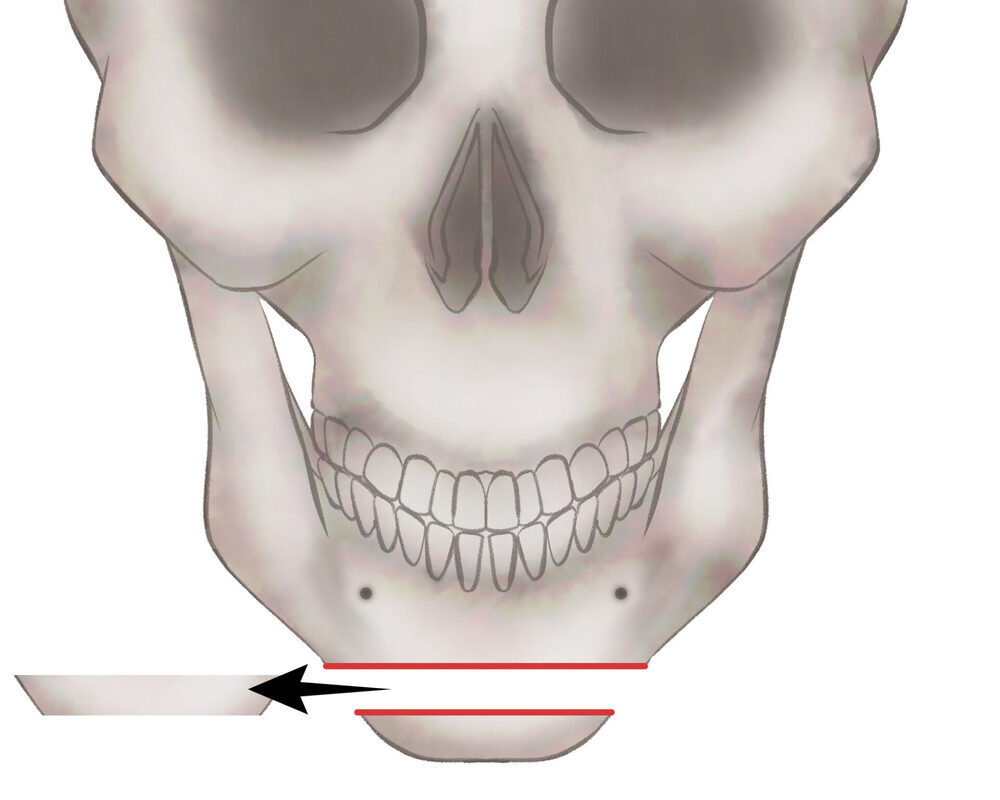

オトガイ骨切り(中抜き)+前方移動

1.切開線をデザインします

2.骨を切り離す、もしくは取り除きます

3.骨を移動させ段差を削ります

4.プレートで固定します